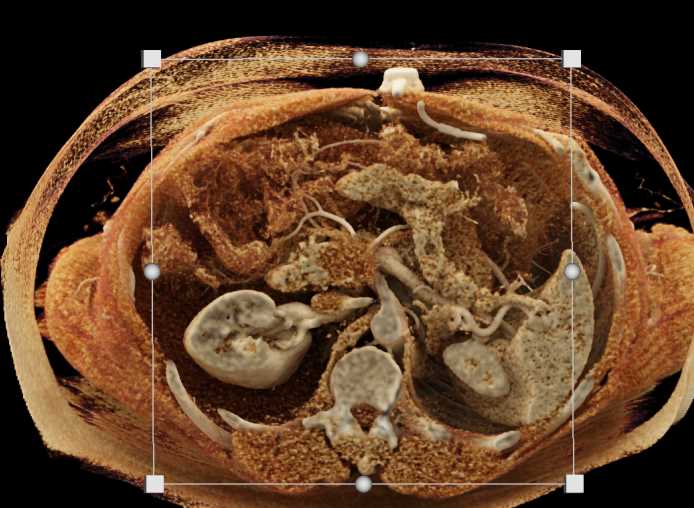

Neuroendocrine Tumor Pancreas